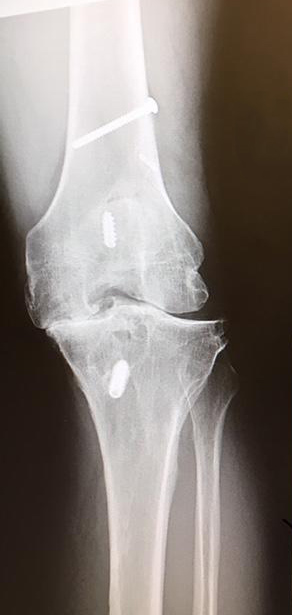

Wow! That's how would describe it. I am veteran of 9 surgeries on my knee and from the moment I stepped foot into HSS it was clear that this was like no other facility I had ever experienced. From the way you are greeted to the way you are treated I highly recommend the hospital. The picture shows just how bad my knee was and thank to Dr. DiFelice, I was walking 6 miles a day in Spain on a family vacation just 4 months after my surgery.